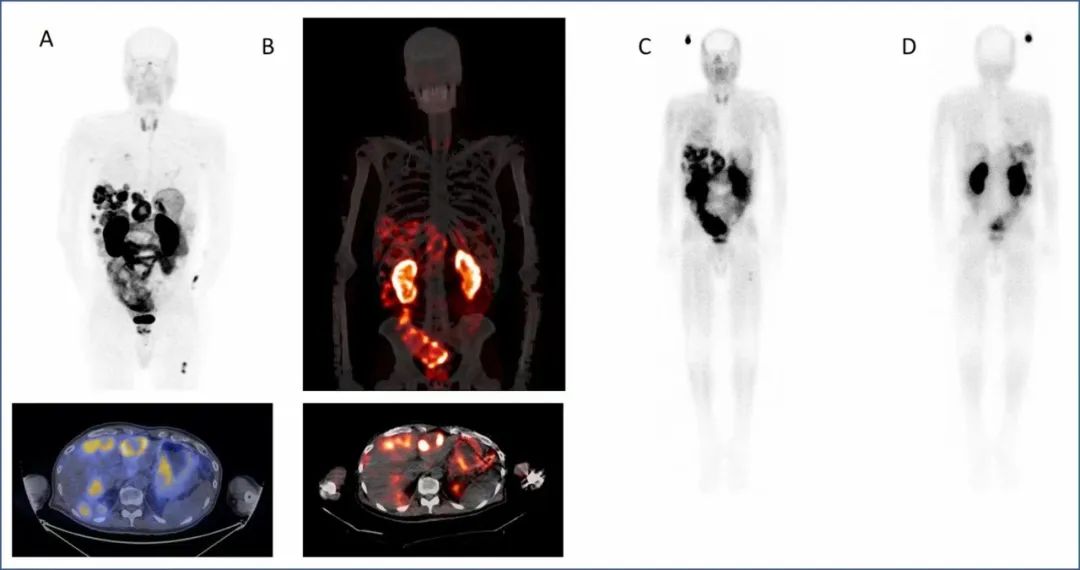

图1. A. 68Ga-DOTA-5G PET/CT 显像 (注射后1小时). B. 177Lu-DOTA-ABM-5G SPECT/CT 显像 (注射后1天). C. 177Lu-DOTA-ABM-5G 全身平面显像 (前位, 注射后1天. D. 177Lu-DOTA-ABM-5G 全身平面显像 (后位,, 注射后1天).

Figure 1. A. 68Ga-DOTA-5G PET/CT images (one hour postinjection). B. 177Lu-DOTA-ABM-5G SPECT/CT images (one day post injection). C. 177Lu-DOTA-ABM-5G whole body planar image (anterior, one day post injection). D. 177Lu-DOTA-ABM-5G whole body planar image (posterior, one day post injection).Abstract 1300. “First-in-human study of the theranostic pair [68Ga]Ga DOTA-5G and [177Lu]Lu DOTA-ABM-5G in pancreatic adenocarcinoma.” Ryan Davis, Cameron Foster, Tanushree Ganguly, Sven Hausner, Edward Kim, Emilie Roncali, and Julie Sutcliffe, University of California, Davis, Davis, California.

Chicago, Illinois (Embargoed until 9:30 a.m. CDT, Monday, June 26, 2023)—A first-in-human evaluation of the novel theranostic pair 68Ga-DOTA-5G / 177Lu-DOTA-ABM-5G has confirmed its ability to successfully detect metastatic pancreatic cancer and visualize targeted treatment of the disease. According to research presented at the 2023 Society of Nuclear Medicine and Molecular Imaging (SNMMI) Annual Meeting, the pair was well tolerated among patients and has the potential to make a significant improvement in the clinical care and treatment of patients with metastatic pancreatic cancer, as well as other cancers. A grouping of 68Ga-DOTA-5G and 177Lu-DOTA-ABM-5G images has been selected as the 2023 SNMMI Henry N. Wagner, Jr., Image of the Year.Each year, SNMMI chooses an image that best exemplifies the most promising advances in the field of nuclear medicine and molecular imaging. The state-of-the-art technologies captured in these images demonstrate the capacity to improve patient care by detecting disease, aiding diagnosis, improving clinical confidence and providing a means of selecting appropriate treatments. This year, the SNMMI Image of the Year was chosen from more than 1,500 abstracts submitted for the meeting.Despite exhaustive testing and some encouraging advances in first- and second-line treatments, pancreatic cancer remains the most lethal type of cancer. The American Cancer Society estimates that more than 64,000 people will be diagnosed with pancreatic cancer in 2023, and more than 50,000 of them will die from the disease—a 5-year survival rate of only 12%.“Poor patient outcomes are due partly to the late stage at which the majority of patients are diagnosed and partly to the limited and relatively ineffective treatment options,” stated Julie L. Sutcliffe, PhD, professor of internal medicine and biomedical engineering, director of the Cyclotron and Radiochemistry Facility in the Center for Molecular and Genomic Imaging and co-director of the Center for Molecular and Genomic Imaging at the University of California–Davis. “Our goal with this study was to develop a theranostic strategy to facilitate both earlier detection and more effective treatment for this devastating malignancy.”The integrin αvβ6 is an epithelial-specific cell surface receptor that is undetectable in healthy adult epithelial cells but is significantly up-regulated in a wide range of epithelial cell-derived cancers, including pancreatic cancer, which makes it a very attractive clinical target for detection and targeted treatment. In the study, researchers in Sutcliffe’s laboratory radiolabeled αvβ6-integrin-targeted peptides to create the theranostic pair 68Ga-DOTA-5G / 177Lu-DOTA-ABM-5G, which was evaluated for its safety and effectiveness.Patients with metastatic or locally advanced pancreatic cancer who demonstrated advanced disease that did not respond to at least one prior standard-of-care treatment were recruited to the study. Patients underwent 68Ga-DOTA-5G PET/CT scans, then vital signs, blood samples and EKG were checked one and seven days after imaging. Patients with lesions with an SUVmax more than two times the normal lung or liver uptake were eligible for 177Lu-DOTA-ABM-5G treatment. Eligible patients received a single treatment with 177Lu-DOTA-ABM-5G and underwent whole body planar imaging and SPECT/CT imaging at approximately one and seven days following administration for evaluation of biodistribution and dosimetry. Vital signs, blood samples and EKG were checked one, seven and 14 days after the treatment.To date, 17 patients have been imaged with 68Ga-DOTA-5G PET/CT and 14 patients have been treated with 177Lu-DOTA-ABM-5G. Both the 68Ga-DOTA-5G and 177Lu-DOTA-ABM-5G agents were well tolerated, and no drug-related serious adverse events were observed. 68Ga-DOTA-5G PET/CT imaging was able to detect bone, lung and hepatic metastasis, and the 177Lu-DOTA-ABM-5G was taken up and retained by the lesions detected by 68Ga-DOTA-5G PET/CT imaging. The average absorbed doses to kidneys and bone marrow (respectively) obtained to date are 3.7 and 0.01 Gy for dose level 1 (25mCi), 6.93 and 0.02 Gy for dose level 2 (50 mCi), 10.03 and 0.03 Gy for dose level 3 (100 mCi), and 14.56 and 0.04 Gy for dose level 4 (150 mCi).“Results from this Phase I trial will pave the way for additional clinical trials in patients with other malignancies including, but not limited to, non-small cell lung cancer, breast cancer, and head and neck cancer,” Sutcliffe said. “The promising pharmacokinetic profile of the 177LuDOTA-ABM-5G therapy suggests that off-target adverse events are not expected, posing a major improvement over current treatments, which are known to cause bone marrow toxicity, hepatobiliary toxicity and cardiotoxicity. This approach has the potential to significantly improve the clinical care and treatment for patients with metastatic disease.”“Findings from this study will add to the rapidly advancing landscape of theranostics,” noted SNMMI Scientific Program chair Heather Jacene, MD. “This new theranostic approach to detecting and treating pancreatic cancer, as shown in the Image of the Year, is a prime example of how personalized medicine can noninvasively detect disease, appropriately select and effectively treat patients, and have a significant, positive impact on the lives of many.”The Phase I arm of this study will be completed in the summer of 2023, and researchers anticipate that a second trial in patients with metastatic non-small cell lung cancer will open to enrollment in fall 2023. A third trial for patients with metastatic carcinoma of any primary origin is expected to commence in the winter of 2023.